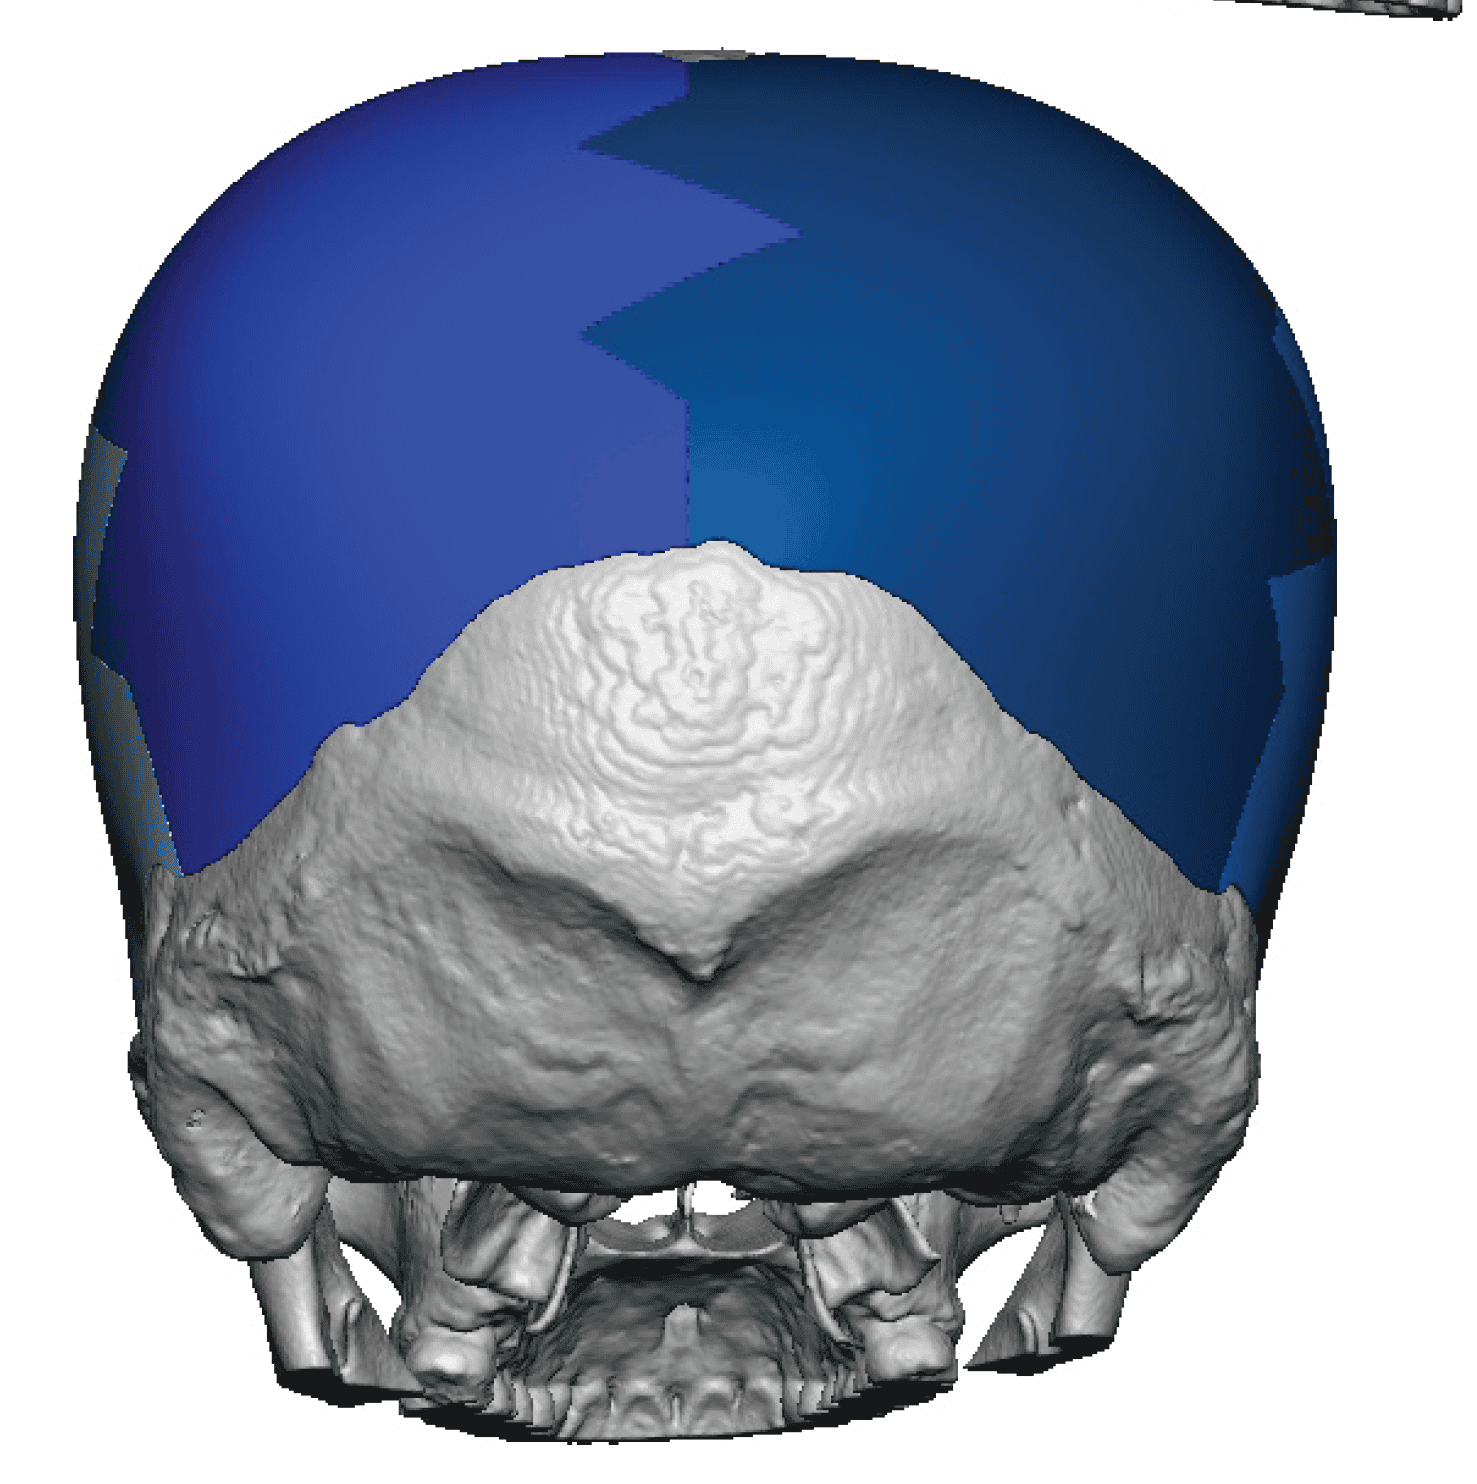

Severe narrowing skull deformity from prior sagittal craniosynostosis repair as an adult.

Complete replacement of entire skull by a custom implant with temporal fat injections.

Severe narrowing skull deformity from prior sagittal craniosynostosis repair as an adult.

Complete replacement of entire skull by a custom implant with temporal fat injections.